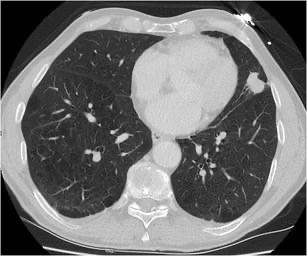

данные и локализацию первичного немелкоклеточного рака в паренхиме лёгкого без прорастания висцеральной плевры, оптимальным объёмом оперативного вмешательства с точки зрения онкологического радикализма и показателей выживаемости, является _________ с удалением регионарных лимфоузлов

2951. Учитывая представленные на томографическом срезе данные и локализацию первичного немелкоклеточного рака в паренхиме лёгкого без прорастания висцеральной плевры, оптимальным объёмом оперативного вмешательства с точки зрения онкологического радикализма и показателей выживаемости, является _________ с удалением регионарных лимфоузлов